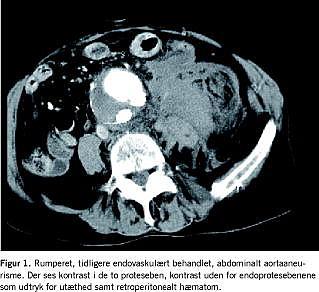

AMI blev afkræftet, og der blev foretaget akut CT af abdomen med kontrast. Denne viste et 6,5 cm bredt abdominalt aortaaneurisme, endoprotese i aorta og begge iliacasystemer samt et stort retroperitonealt hæmatom, som displacerede venstre nyre betydeligt (Figur 1 ). Som tegn på endoleak-betinget ruptur var der kontrast i aneurismesækken. Skanningen viste i øvrigt et torakalt aortaneurisme.